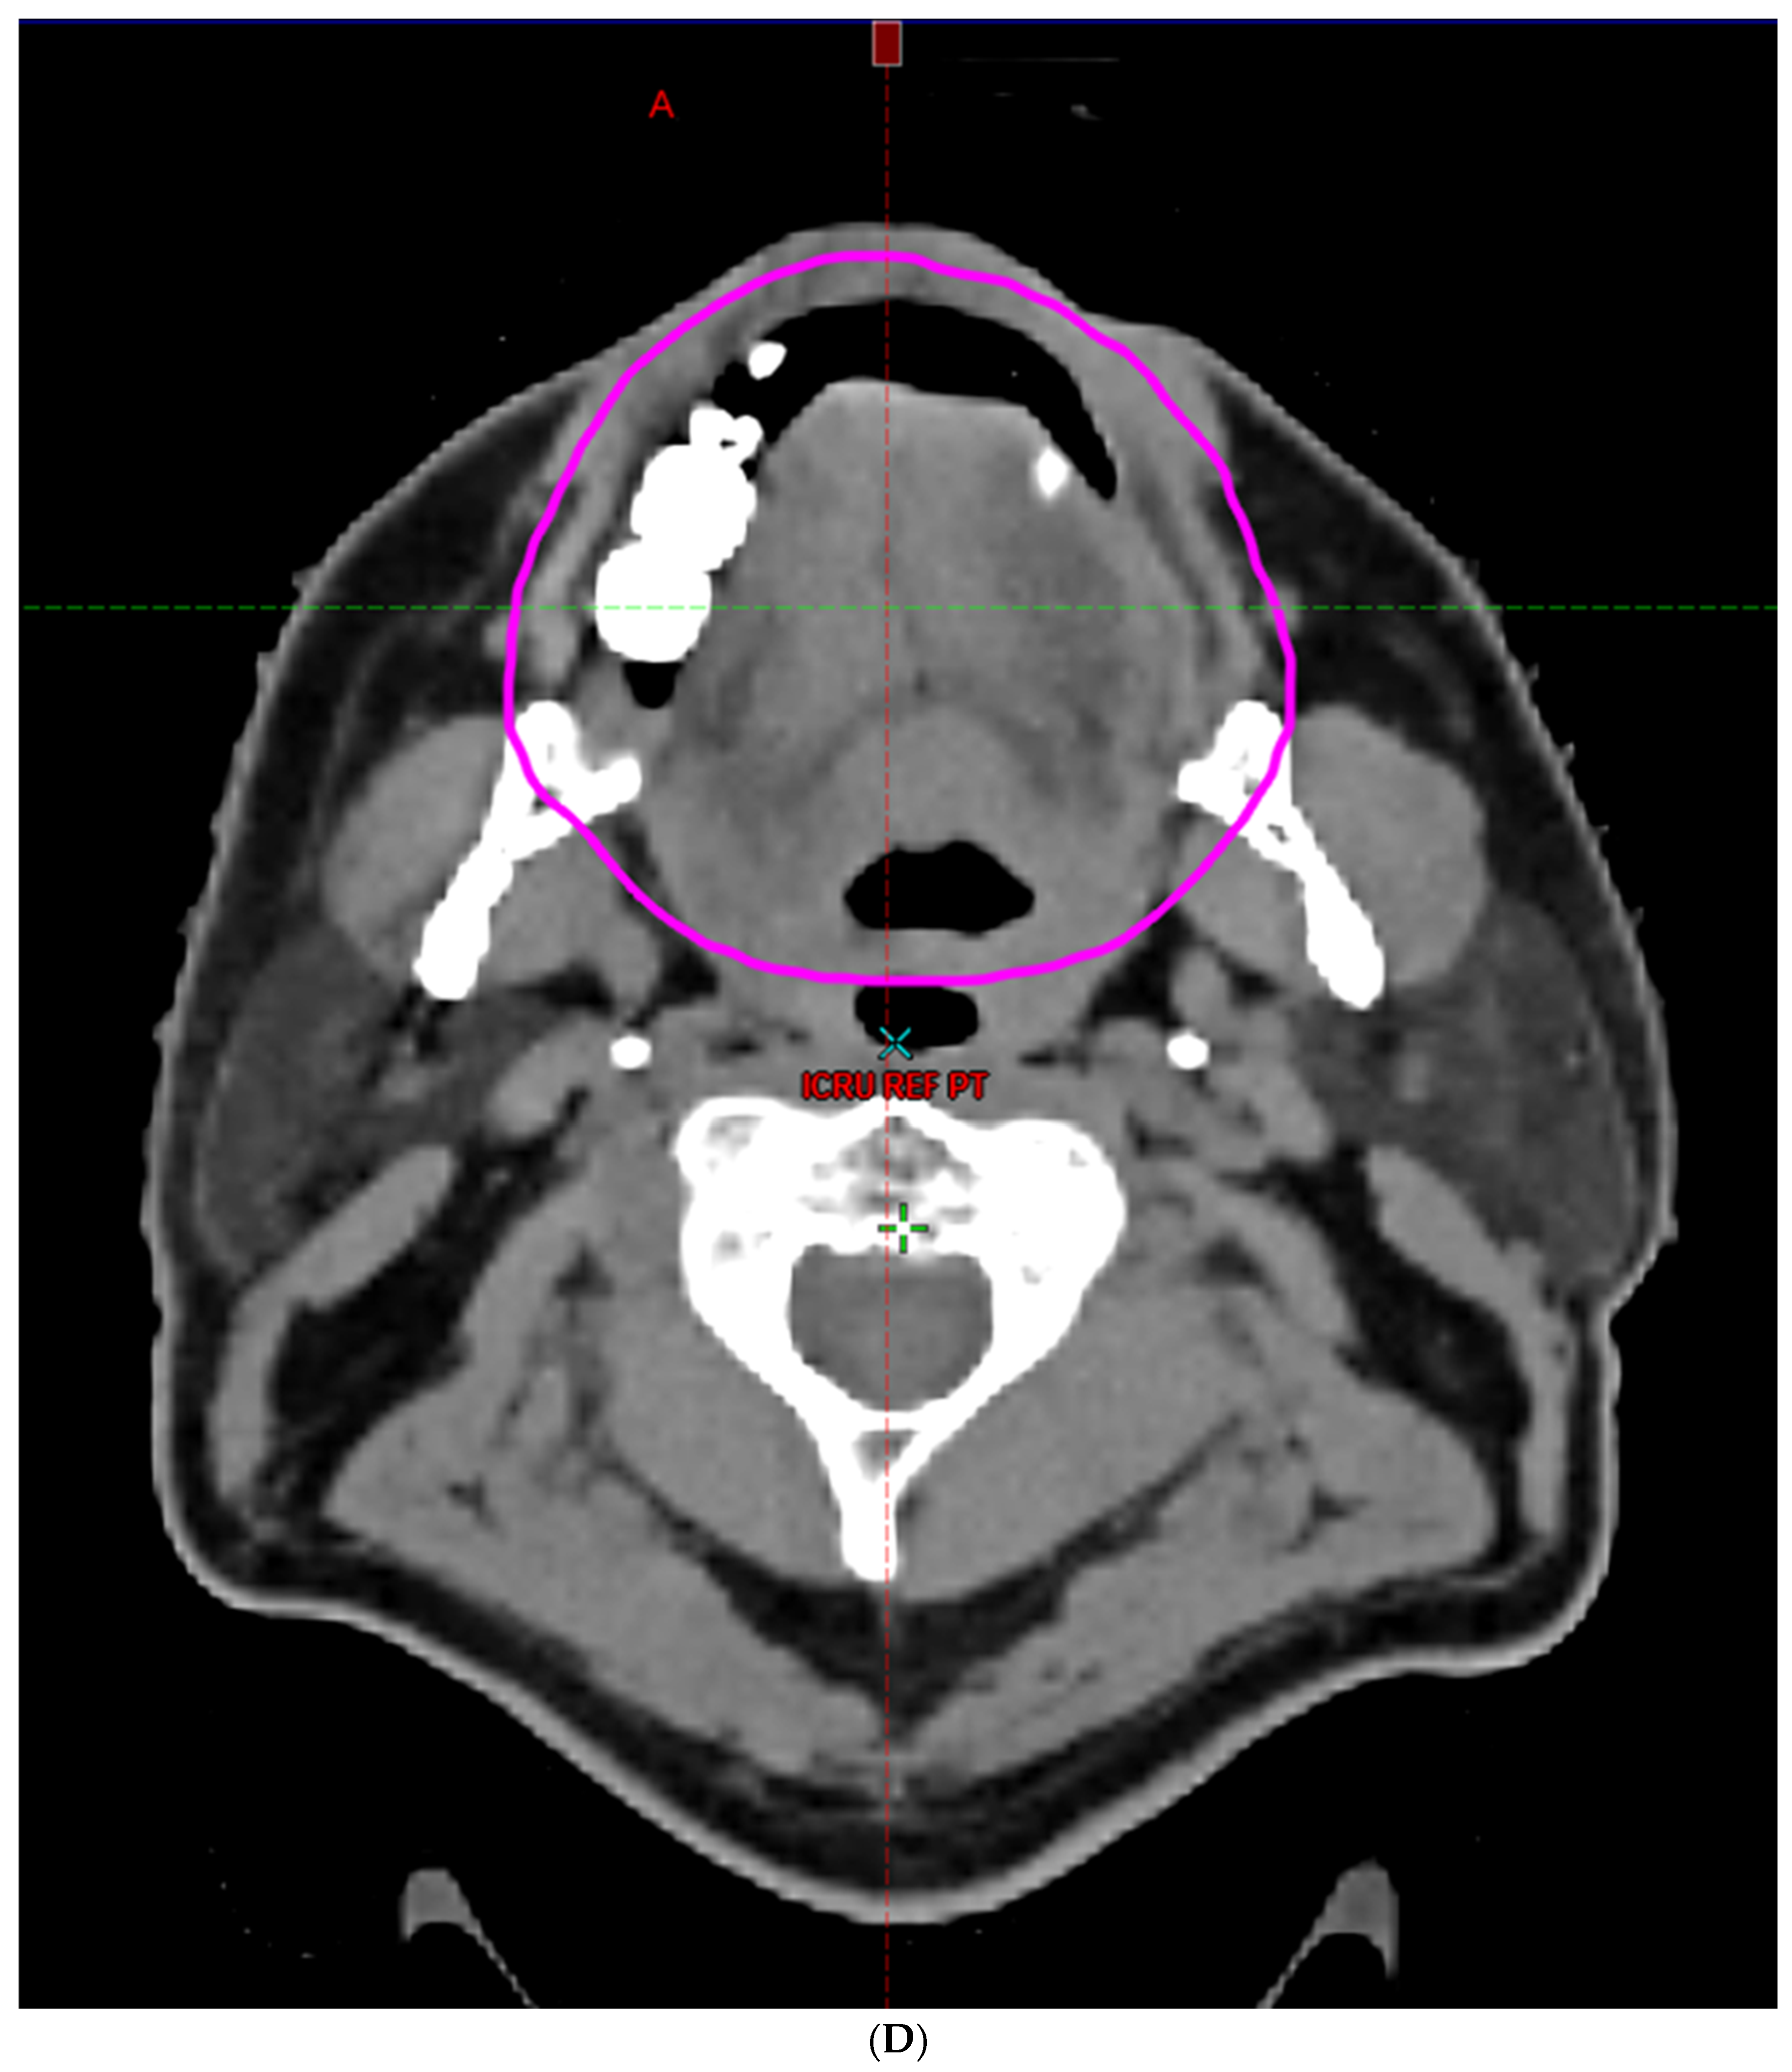

- Hoebers, F.; Yu, E.; Thorstad, W.; O’Sullivan, B.; Dawson, L.A.; Hope, A. A Pragmatic Contouring Guideline for Salivary Gland Structures in Head and Neck Radiation Oncology. The MOIST Target. Am. J. Clin. Oncol. 2013, 36, 70–76. [Google Scholar] [CrossRef]

- Brouwer, C.L.; Steenbakkers, R.J.; Bourhis, J.; Budach, W.; Grau, C.; Grégoire, V.; Van Herk, M.; Lee, A.; Maingon, P.; Nutting, C.; et al. CT-based delineation of organs at risk in the head and neck region: DAHANCA, EORTC, GORTEC, HKNPCSG, NCIC CTG, NCRI, NRG Oncology and TROG consensus guidelines. Radiother. Oncol. 2015, 117, 83–90. [Google Scholar] [CrossRef]

- Li, K.; Yang, L.; Hu, Q.-Y.; Chen, X.-Z.; Chen, M.; Chen, Y. Oral Mucosa Dose Parameters Predicting Grade ≥ 3 Acute Toxicity in Locally Advanced Nasopharyngeal Carcinoma Patients Treated with Concurrent Intensity-Modulated Radiation Therapy and Chemotherapy: An Independent Validation Study Comparing Oral Cavity versus Mucosal Surface Contouring Techniques. Transl. Oncol. 2017, 10, 752–759. [Google Scholar] [CrossRef]

- Sun, Y.; Yu, X.-L.; Luo, W.; Lee, A.W.; Wee, J.T.S.; Lee, N.; Zhou, G.-Q.; Tang, L.-L.; Tao, C.-J.; Guo, R.; et al. Recommendation for a contouring method and atlas of organs at risk in nasopharyngeal carcinoma patients receiving intensity-modulated radiotherapy. Radiother. Oncol. 2014, 110, 390–397. [Google Scholar] [CrossRef]

- Dean, J.A.; Welsh, L.C.; Gulliford, S.L.; Harrington, K.J.; Nutting, C.M. A novel method for delineation of oral mucosa for radiotherapy dose–response studies. Radiother. Oncol. 2015, 115, 63–66. [Google Scholar] [CrossRef]